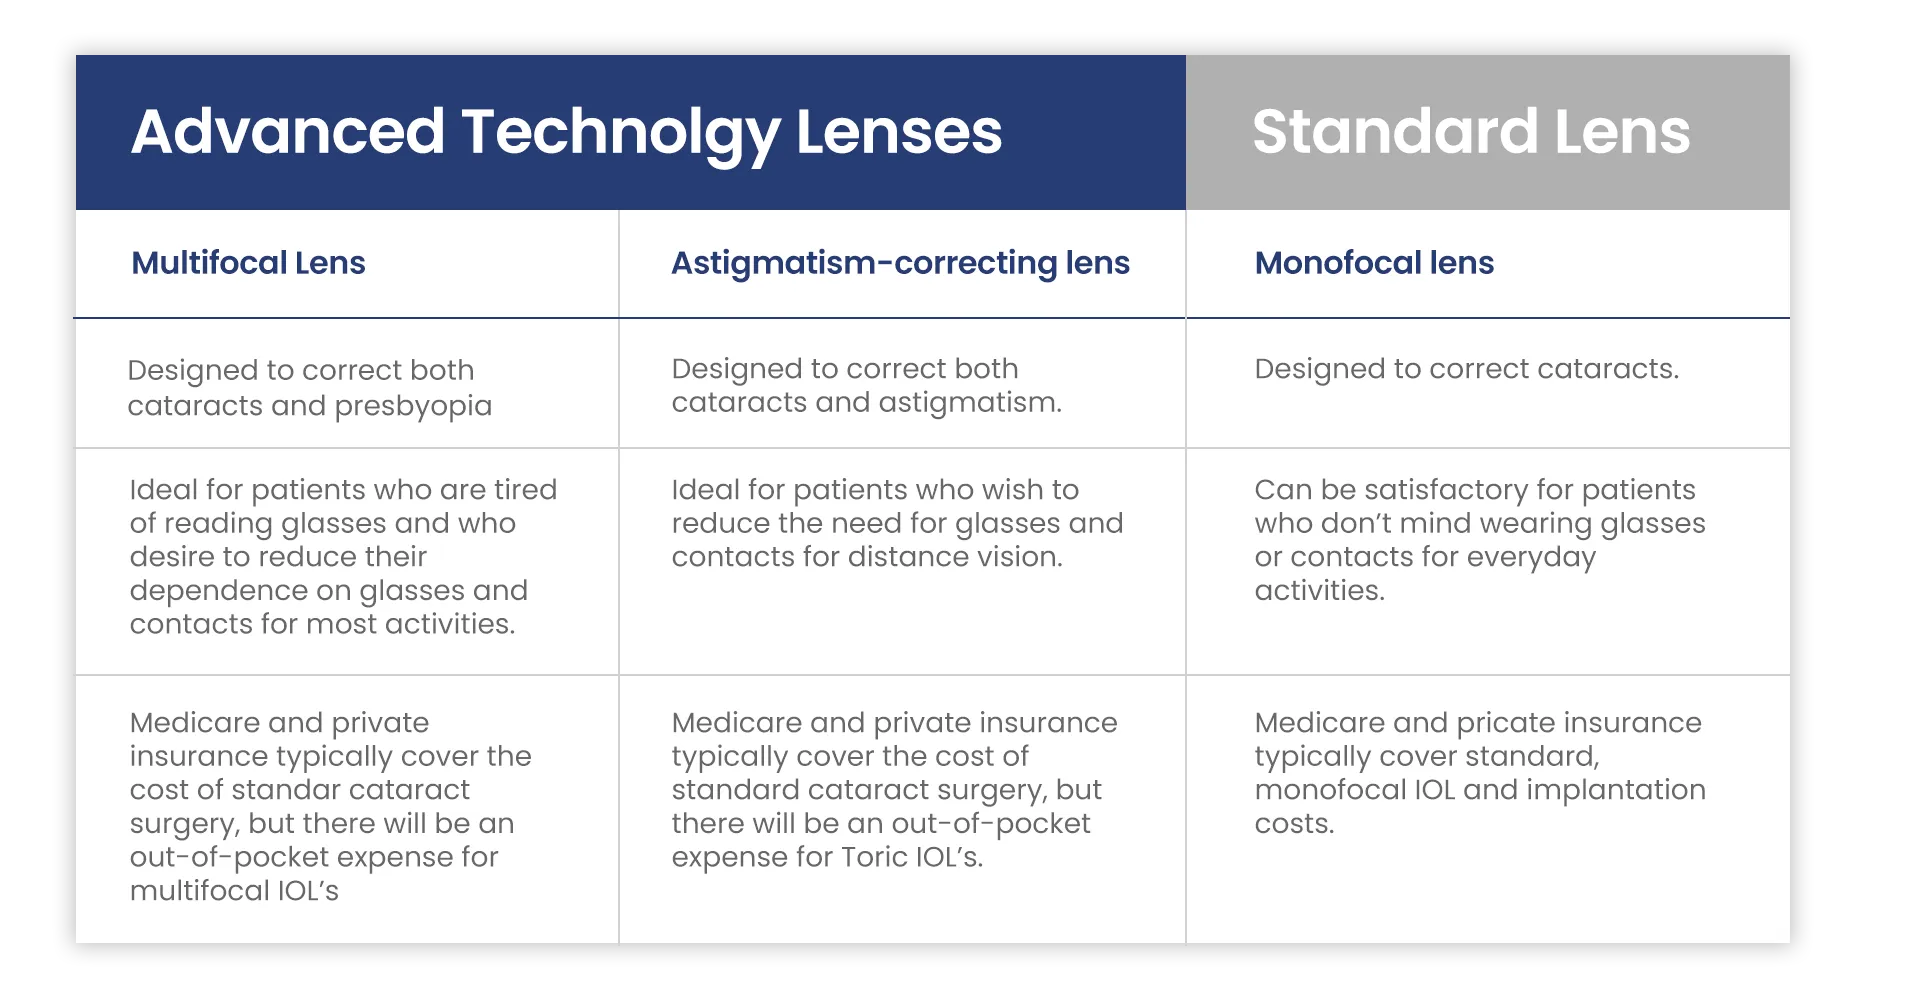

Cataract surgery is an operation performed to remove the cloudy proteins from your lens. The lens then must be replaced with a new, clear artificial lens called an intraocular lens (IOL). Every patient who has cataract surgery will get a new IOL implanted. This is the standard of care. The good news is that cataract surgery is an opportunity to improve your vision, correct your astigmatism, enhance your focus and decrease the dependency on glasses should you choose.

Intraocular Lens Choices

Choosing an intraocular lens for your cataract surgery is an important, once-in-a-lifetime decision. Your new lens will change the way you see the world around you, so you will want to choose the lens that’s right for you. There is nothing more in this world that you will use every day more than your eyesight. Because of this, many people feel that paying extra for an advanced-technology lens, such as the PanOptix lens, is a wise investment.

After a thorough eye exam and the necessary testing has been performed, Dr. Pine will discuss with you the different choices you may have when it comes to selecting the correct IOL for you. Not all lenses are good options for every patient. Many factors, such as health of the eye, astigmatism and your personal visual needs will play a role in your decision. The single most important question you can answer for Dr. Pine is “What would you like out of your vision after cataract surgery?’

Cataract surgery is an operation performed to remove the cloudy proteins from your lens. The lens then must be replaced with a new, clear artificial lens called an intraocular lens (IOL). Every patient who has cataract surgery will get a new IOL implanted. This is the standard of care. The good news is that cataract surgery is an opportunity to improve your vision, correct your astigmatism, enhance your focus and decrease the dependency on glasses should you choose.

Choosing an intraocular lens for your cataract surgery is an important, once-in-a-lifetime decision. Your new lens will change the way you see the world around you, so you will want to choose the lens that’s right for you. There is nothing more in this world that you will use every day more than your eyesight. Because of this, many people feel that paying extra for an advanced-technology lens, such as the PanOptix lens, is a wise investment.

After a thorough eye exam and the necessary testing has been performed, Dr. Pine will discuss with you the different choices you may have when it comes to selecting the correct IOL for you. Not all lenses are good options for every patient. Many factors, such as health of the eye, astigmatism and your personal visual needs will play a role in your decision. The single most important question you can answer for Dr. Pine is “What would you like out of your vision after cataract surgery?’